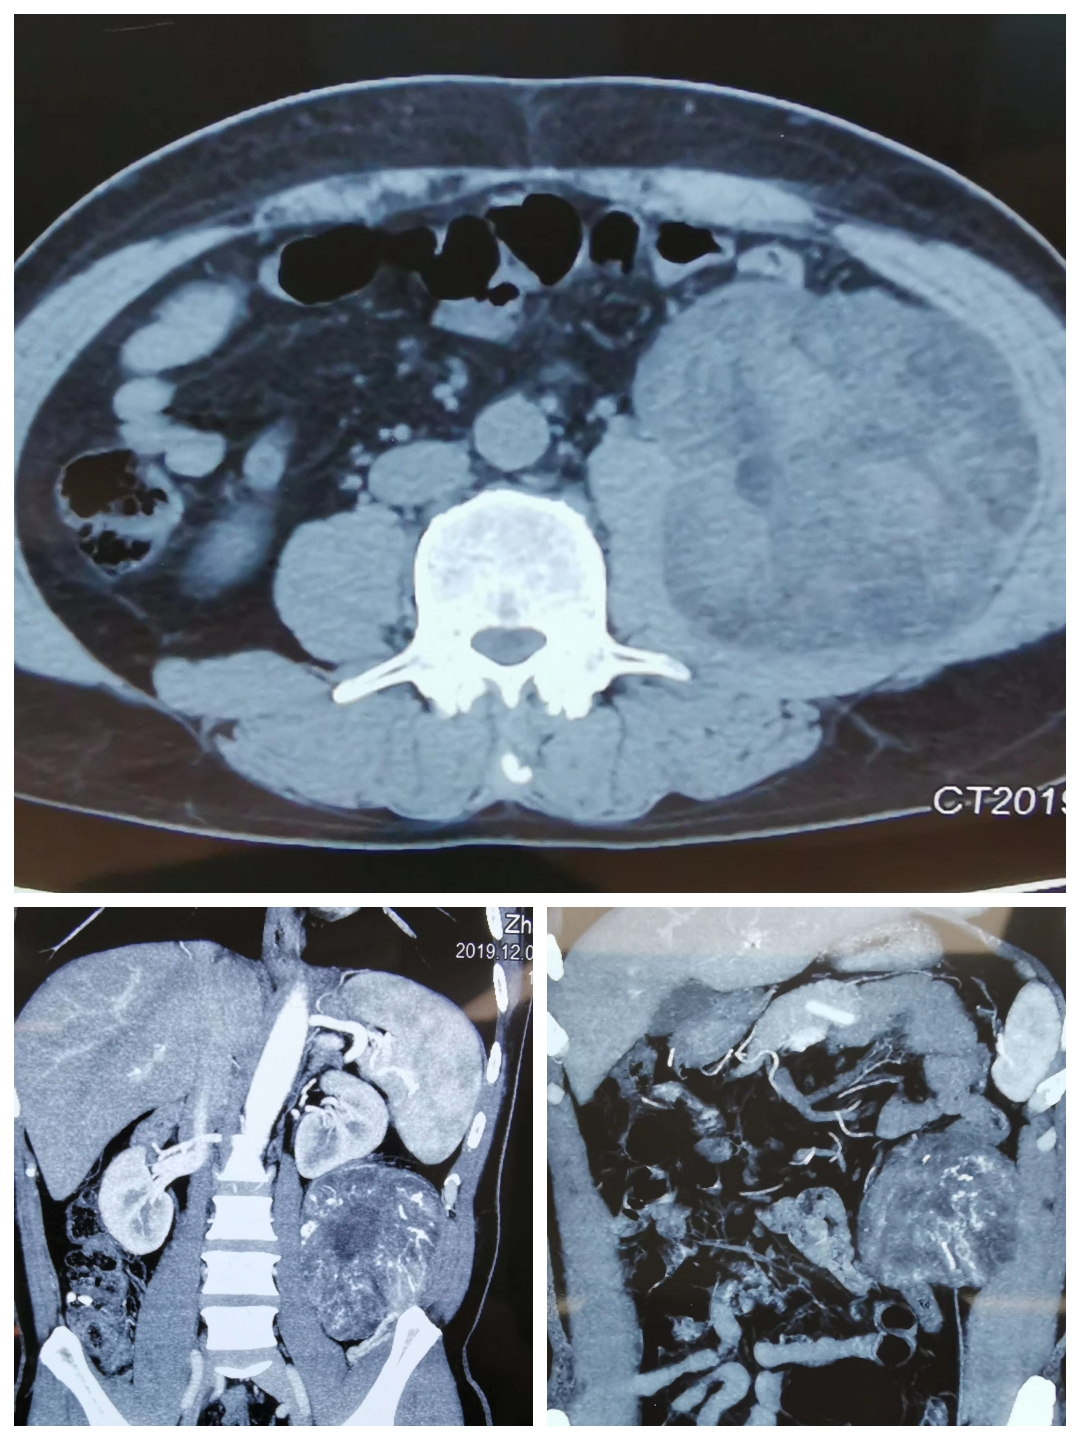

2019年12月22日,是我国传统二十四节气中的冬至,在家家户户团聚在一起包饺子、吃饺子之际,二人麻将指南网 外二科(结直肠肛门疾病专业、综合外科)在麻醉手术室、检验科等相关兄弟科室的配合下,成功完成一例腹膜后巨大肿瘤切除术。患者男性,主因“左侧腹部憋胀不适6月”而入院。完善腹部CT回报:左中腹部腹膜后巨大占位性病变,考虑脂肪肉瘤可能性大。患者近期有发热表现,不排除肿瘤出血、坏死可能。经过充分的术前评估,翟春宝主任决定限期行根治性手术治疗。

手术标本,大小约13cm×13cm×15cm,包膜完整,脂肪肉瘤可能